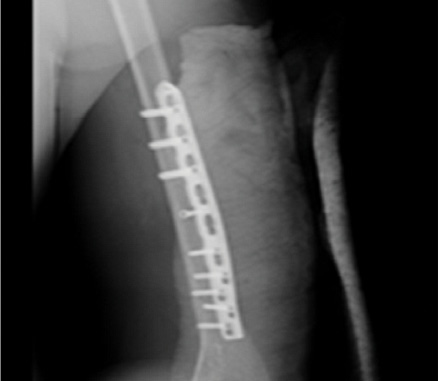

Taking into account the plate location on the template, a surgical approach of a certain shape and length was planned taking into account the anatomical structures located in the projection of the fracture line and the plate. Intraoperatively, there were no complications, injuries of the anatomical structures, or difficulties with plate installation and osteosynthesis of bone fragments. The bone integrity was restored, which was confirmed by the control X-ray of the humerus in the postoperative period (Figure 4). The follow-up examination of the patient was performed. Consolidation of the fracture was noted 3 months after the surgery.

Figure 4. A bone plate modeled on the individual stereolithographic template.

Рисунок 4. Накостная пластина, отмоделированная по индивидуальному стереолитографическому шаблону.

Using this template, taking into account the course of the fracture line, the optimal position of the plate was chosen. The latter was modeled using the template (Figure 5).

Figure 5. a) Intraoperative view after osteosynthesis of the left humerus with a preoperatively modeled plate. b) Postoperative radiography of the left humerus.

Рисунок 5. а) Интраоперационный вид после остеосинтеза левой плечевой кости предоперационно моделированной пластиной. б) Послеоперационная рентгенография левой плечевой кости.